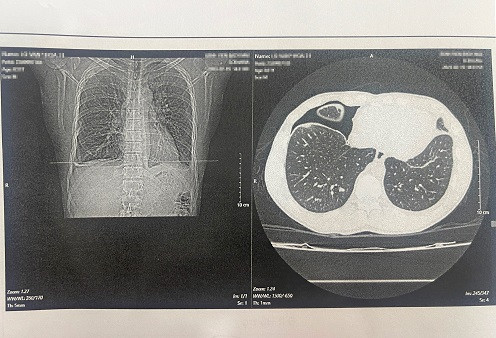

Ăn món gỏi cua sống, một nam thanh niên bị nhiễm “sán lá phổi” ảnh 2Hình ảnh phim chụp trên bệnh nhân sán lá phổi. (Ảnh: PV/Vietnam+)